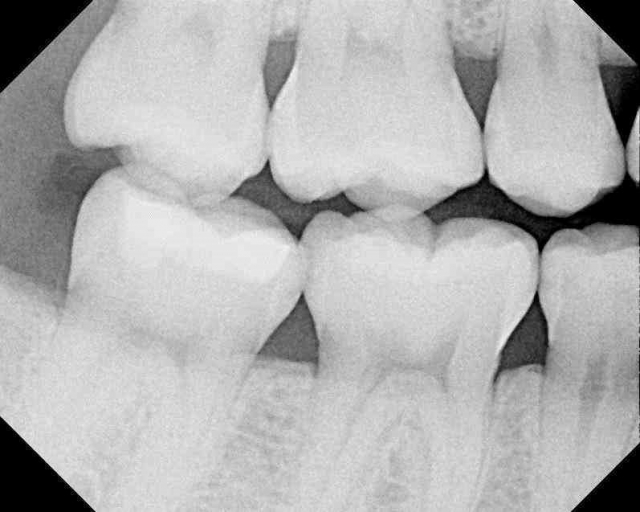

Patient 1: Tooth #12

This patient, who presented in 2015, brought her 2013 black-and-white image with her (the first images above). The second set of black and white images are from 2015. Notice the change in the interproximal caries. Even with a significant change (hypothetical) in a patient’s habit and fluoride delivery, how do these types of caries arrest predictably?